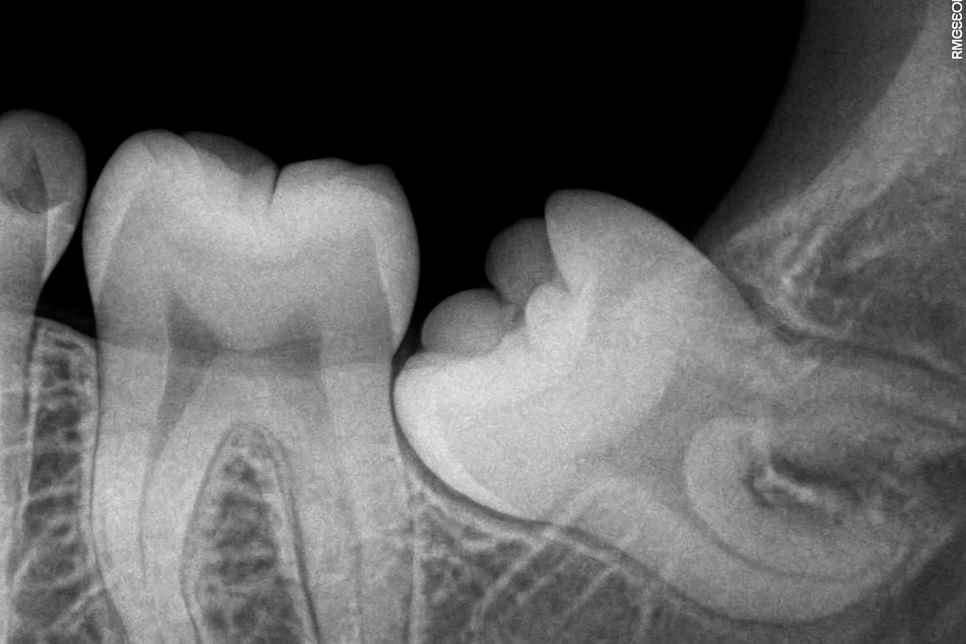

매복 사랑니와 같이 아직 맹출되지 않았을 때는

자리 잡고 있는 방향과 위치도 확인할 수 있어

향후 일어날 수 있는 문제들을

미리 예측하고 대비할 수 있습니다.